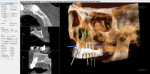

A | 360dps

Figure 1 | 360dps™ offers extensive diagnostic functionalities with a focus on making clinical tasks more efficient and controllable. Diagnosing and planning treatments can be done with a level of predictability and safety. Enhance your diagnostics with combined 2D and 3D views.

866-360-6622

360imaging.com